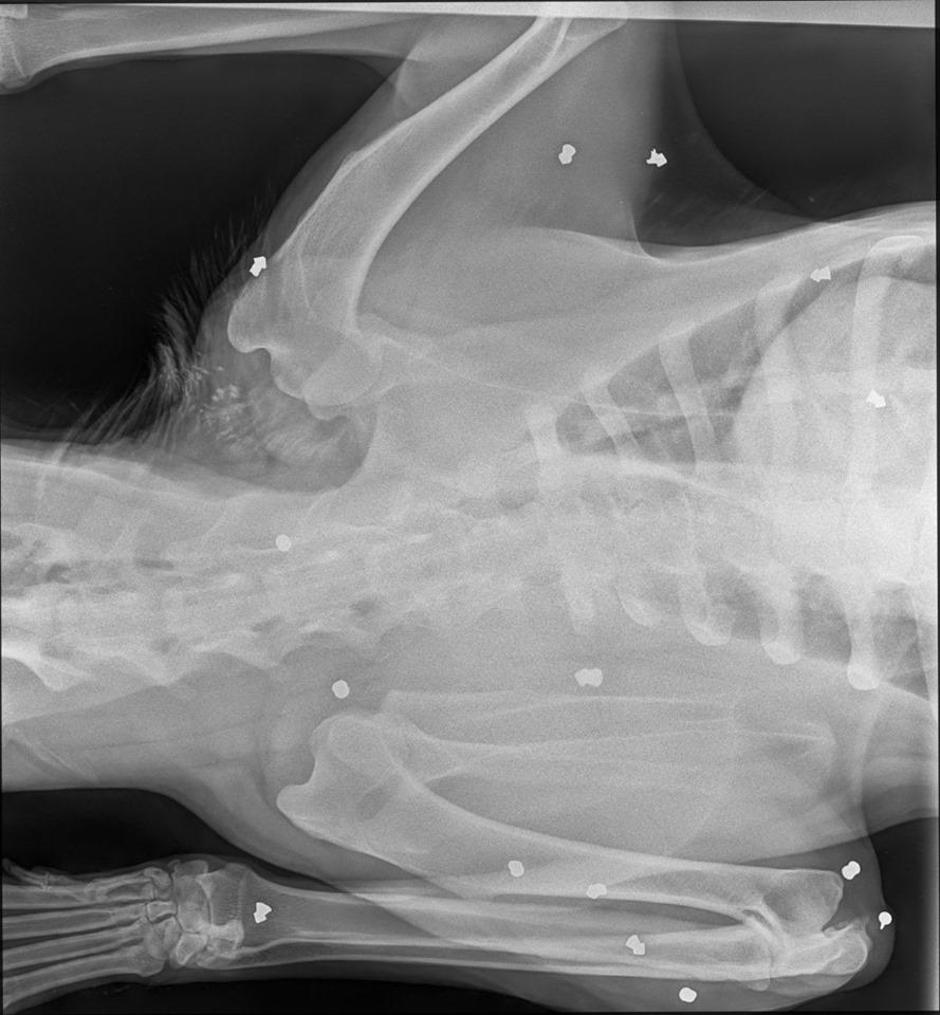

Kujica Liberty zaklon je pronašla u napuštenoj kući na periferiji jednog slavonskog grada, ali i tu je smetala. Onima koji nemaju milosti za život pa su je pokušali dokrajčiti, ne mareći što se brine za devet malih života. Da nije bilo jedne Mateje i njezine mame, koje su psećoj obitelji nosili hranu i vodu, pitanje je bi li Liberty uspjela preživjeti, bi li uspjela zaštiti svoju mladunčad. Kad su je volonteri doveli veterinaru imala je duboku ubodnu ranu na vratu, vjerojatno od noža, ali ono što je pokazao rentgen sve ih je ostavilo bez riječi.

– Netko se igrao Ramba, u njezinom je tijelu najmanje 15 metaka. Detektor metala alarmirao je da ih ima još, ali nisu je okretali već su brzo vadili metke koji nisu bili duboko u tijelu – objašnjava volonterka vinkovačke udruge Rocco, koja se sada brine o kujici. Na njihovoj Facebook stranici objavljen je i poziv za pomoć, jer sami ne mogu.